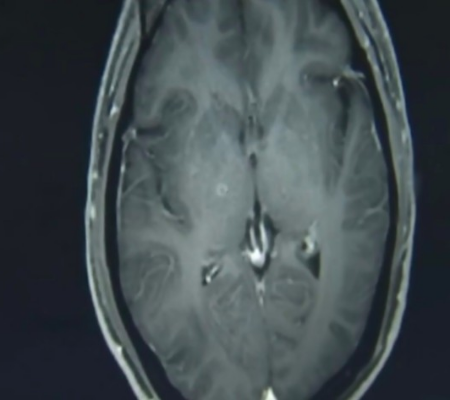

(Foto: Reprodução Hospital da Universidade de Zhejiang)Com a persistência dos sintomas, o chinês foi hospitalizado novamente e os médicos puderam realizar exames de ressonância magnética. Analisando as imagens do cérebro de Zhu, os profissionais perceberam centenas de calcificações e lesões no órgão.

(Foto: Reprodução Hospital da Universidade de Zhejiang)